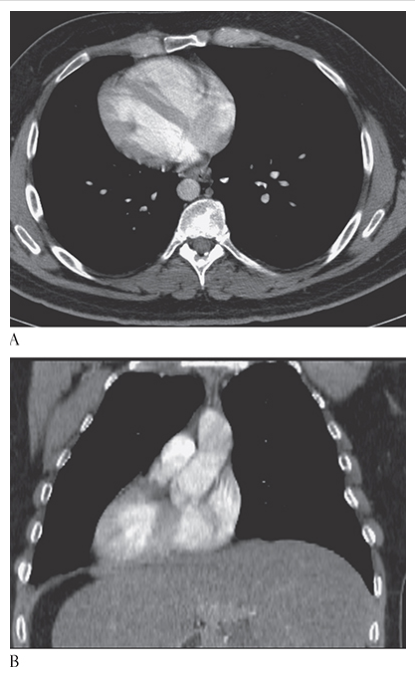

Atrial Myxoma. Contrast-enhanced sagittal MPR CT shows a round filling defect/mass in the left atrium consistent with a myxoma (arrow).